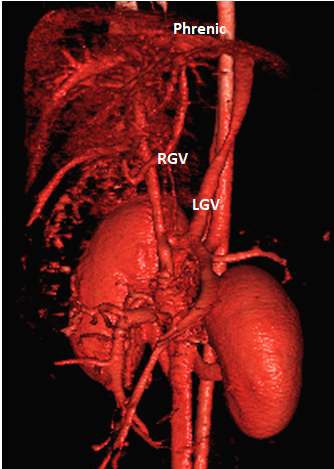

(Phrenic vein entrance)

Does the RIGHT GASTRIC VEIN (RGV) contribute blood to the shunt?

WEISSE 2022

slide34

POST-HEPATIC ENTRANCE